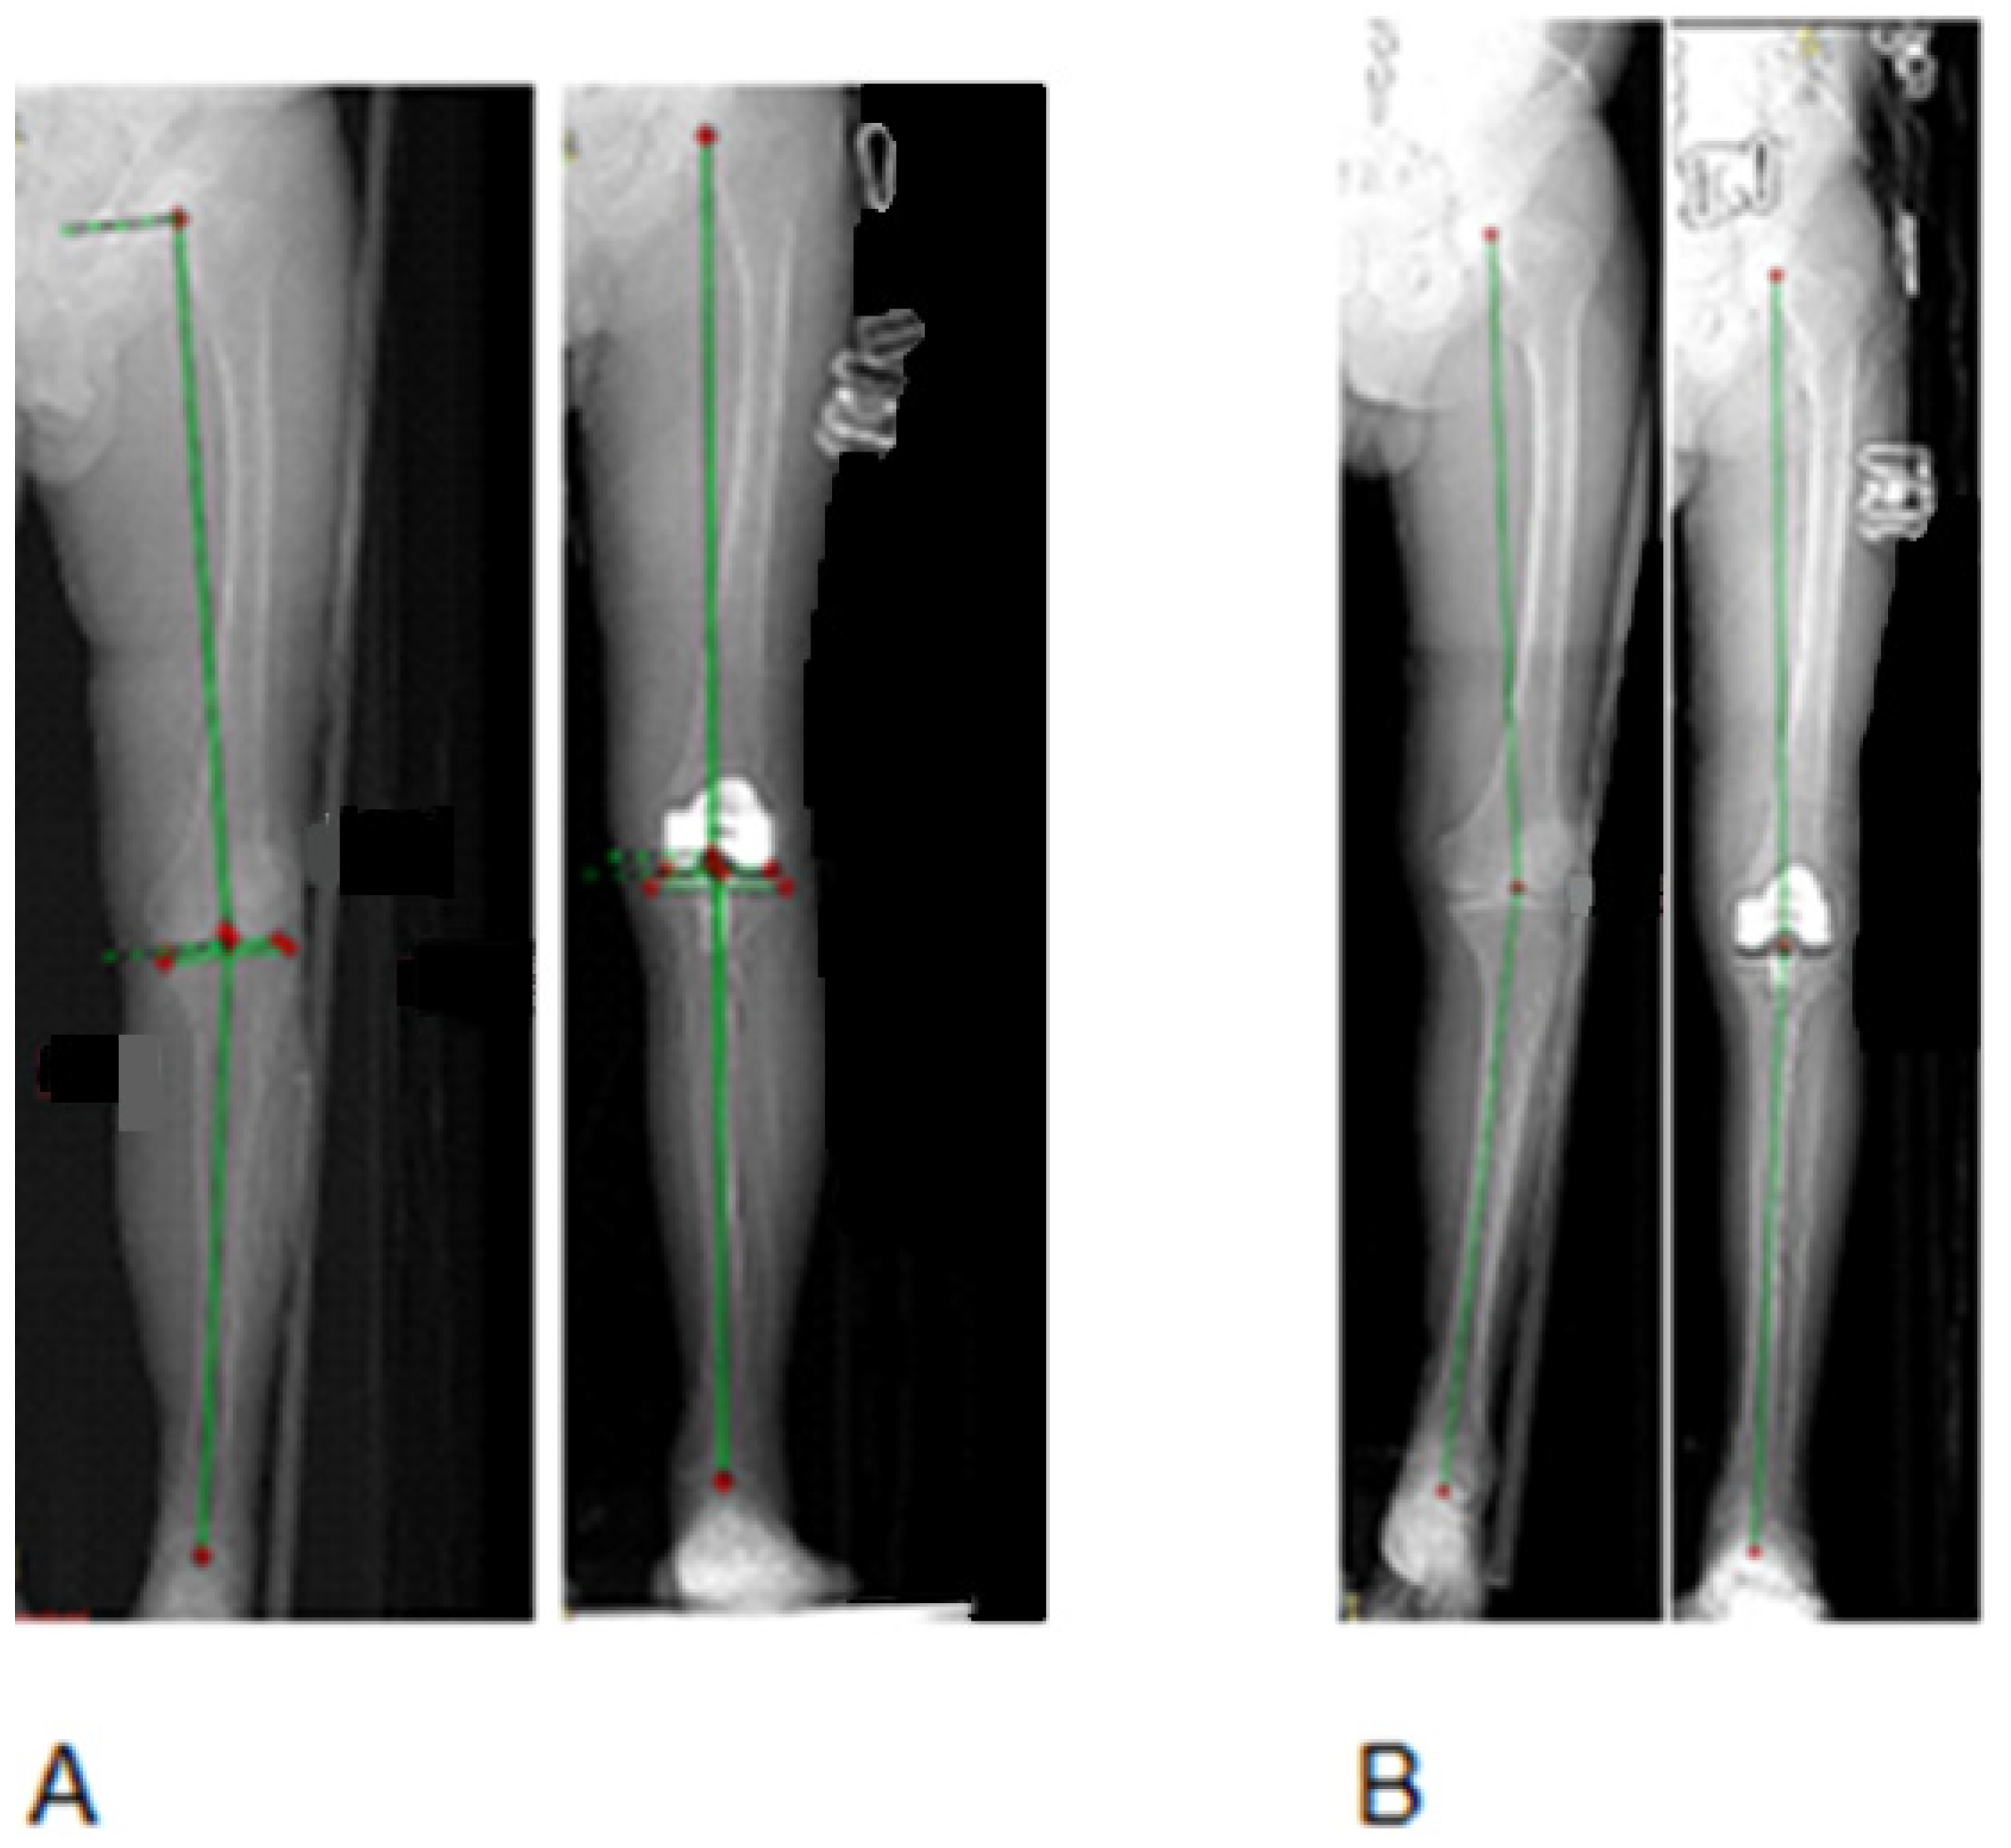

2.6. Radiological Evaluation

3.2. Radiographic Alignment